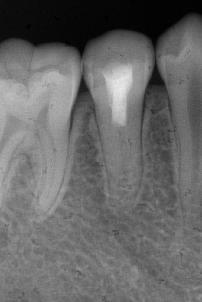

通过牙髓再生治疗,促进牙髓坏死的年轻恒牙牙根进一步发育,牙髓活力测试呈阳性 。

术后1